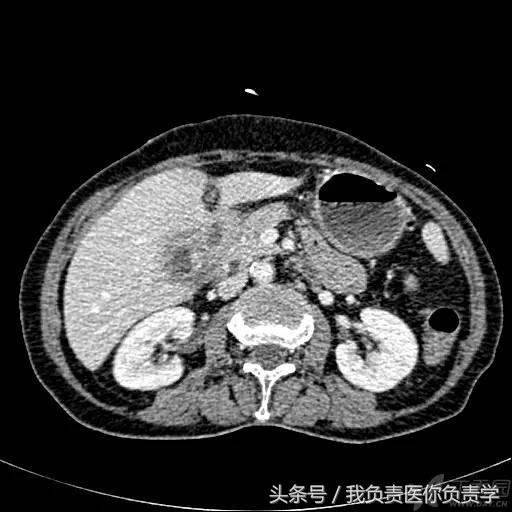

图6和7为相应CT表现